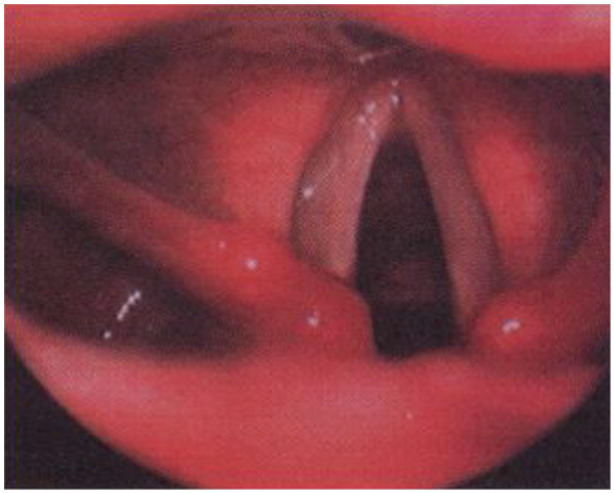

Objectives: Bilateral recurrent nerve damage still represents one of the main complications following thyroid surgery, even though the nerve intraoperative monitoring has allowed the decrease of this injury. This observational retrospective study aims to define the onset modalities and the recovery time of different clinical conditions that may occurs after thyroidectomy.

Methods: From a total of 1417 patients who underwent total thyroidectomy for benign tumors between 2017 and 2022 in ENT Unit of University of Campania "L. Vanvitelli," this study involved 30 patients with bilateral vocal folds motility deficit. These patients (28 F, 2 M), aged from 24 to 78 years old (average age 51.7), presented a bilateral vocal fold motility deficit. Five patients of the study developed an acute respiratory failure upon the awakening that required a nasotracheal prolonged safe extubation. The other 25 patients underwent 9 months diagnostic and therapeutic process, which started approximately 30 days after thyroid surgery.

Results: Indeed, there are several outcomes of these complications, like functional laryngeal defects, which are mainly related to respiratory and phonatory activities. These clinical manifestations can evolve in different ways within a context of a wide range of possibilities, from the spontaneous bilateral or monolateral recovery to the necessity of a functional or surgical restoration.